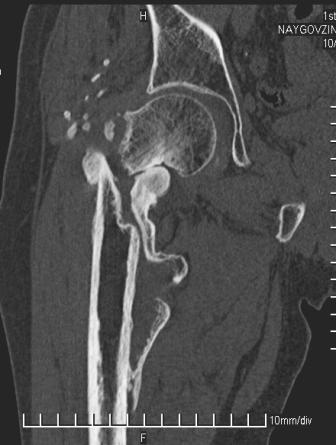

[Ortho] Сросшийся со смещением чрез-подвертельный перелом